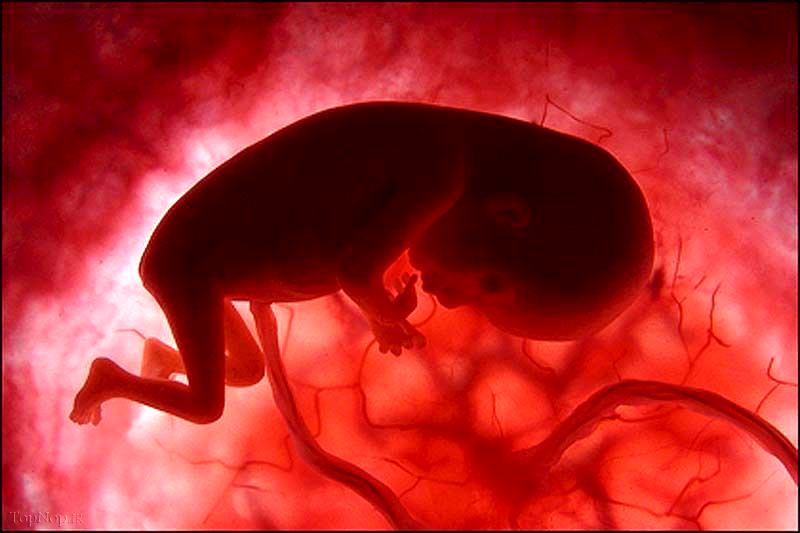

شفافیت نوکال مجموعه ای از مایعات زیر پوست گردن نوزاد است.

این آزمایش ضخامت سیال را اندازه گیری می کند. اگر ضخیم تر از حد طبیعی باشد، به این معنی است که کودک ممکن است به سندرم داون یا سایر ناهنجاری های ژنتیکی مبتلا باشد. این آزمایش همچنین یک تشخیص نیست، اما اندازه گیری خطر را نشان می دهد.

سونوگرافی برای اندازه گیری فضای پر از مایع در نزدیکی پشت گردن جنین (به نام شفافیت نوکال جنین)

سونوگرافی می تواند به تخمین خطر ابتلا به سندرم داون و برخی دیگر از ناهنجاری های کروموزومی کمک کند. می تواند نشان دهد که آیا فضای پشت گردن جنین بزرگ شده است یا خیر. اگر چنین باشد، خطر این ناهنجاری ها افزایش می یابد.